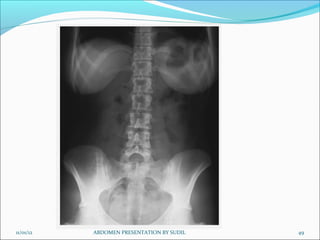

AP-supine (KUB)

Centering of beam:

Equipment setting: ( for screen film combination)

Picture criteria:

 Whole of abdomen from upper abdomen to symphysis pubis.

 Lateral abdominal wall and the properitoneal fat layer.

 Psoas muscle, lower border of liver and the kidneys.

 Ribs and spinous processes of the lumbar vertebra.

 Whole of the urinary tract should be visualized.

 Bowel gas pattern with minimal unsharpness.